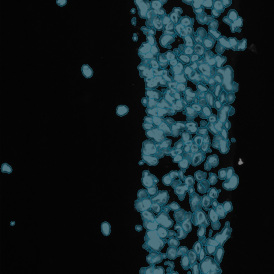

The IHC Angio App detects blood vessels based on appropriate stains (e.g., CD31) and measures overall vessel and lumen areas. The vessel detection can be set to close open stained vessel walls and connect separated vessel sections within a definable distance. As well as vessel number, density, and areas, the App also outputs endothelium and lumina areas.

App Category 2